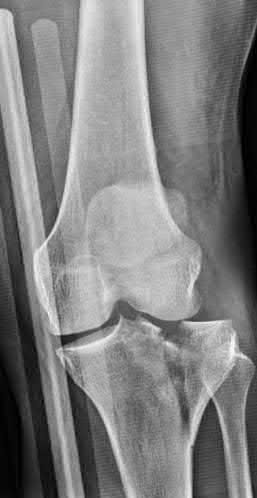

Figures 1 and 2 show the radiographs obtained from a 79-year-old woman who has been experiencing increasing tibial pain 10 years after undergoing revision total knee arthroplasty. No evidence of infection is seen. What is the most appropriate treatment?

Revise the tibial component with a metaphyseal cone and metaphyseal uncemented stem.

Revise the tibial component with a metaphyseal cone and a press-fit diaphyseal-engaging stem.

Revise the tibial component with a long cemented diaphyseal-engaging stem.

Stems are available for cemented and press-fit implantation. To be effective, press-fit stems should engage the diaphysis, as shown in Figures 3 and

They also assist in obtaining correct limb alignment. Short metaphyseal- engaging stems are associated with failure rates that range between 16% and 29%. Cemented stems may be shorter than press-fit stems, because they do not have to engage the diaphysis. Short, fully cemented stems offer the advantage of metaphyseal fixation. Hybrid stem fixation makes use of the metaphysis for cement fixation with metaphyseal cones or sleeves and diaphyseal-engaging press-fit stems.